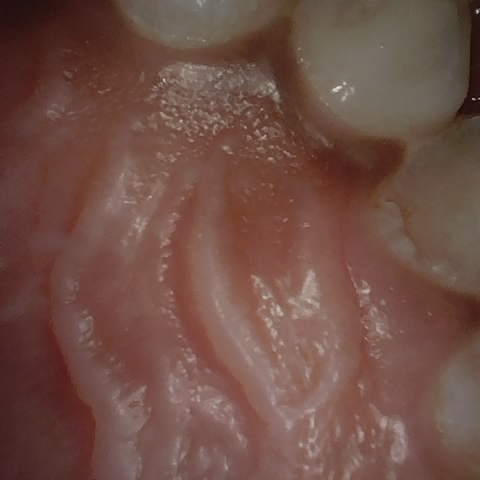

Annotated as "Good"